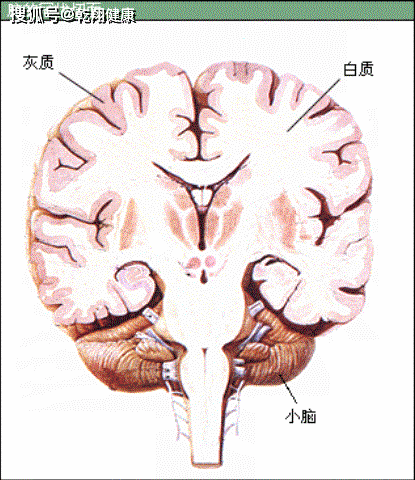

端脑系统解剖学课件ppt 大脑皮质:表面的灰质 大脑髓质:深面的白质 基

部分术语 神经元胞体集聚 灰质 皮质 神经核 白质 髓质 纤维束 髓质

大脑,有灰质(grey matter)和白质(white matter)两部分.